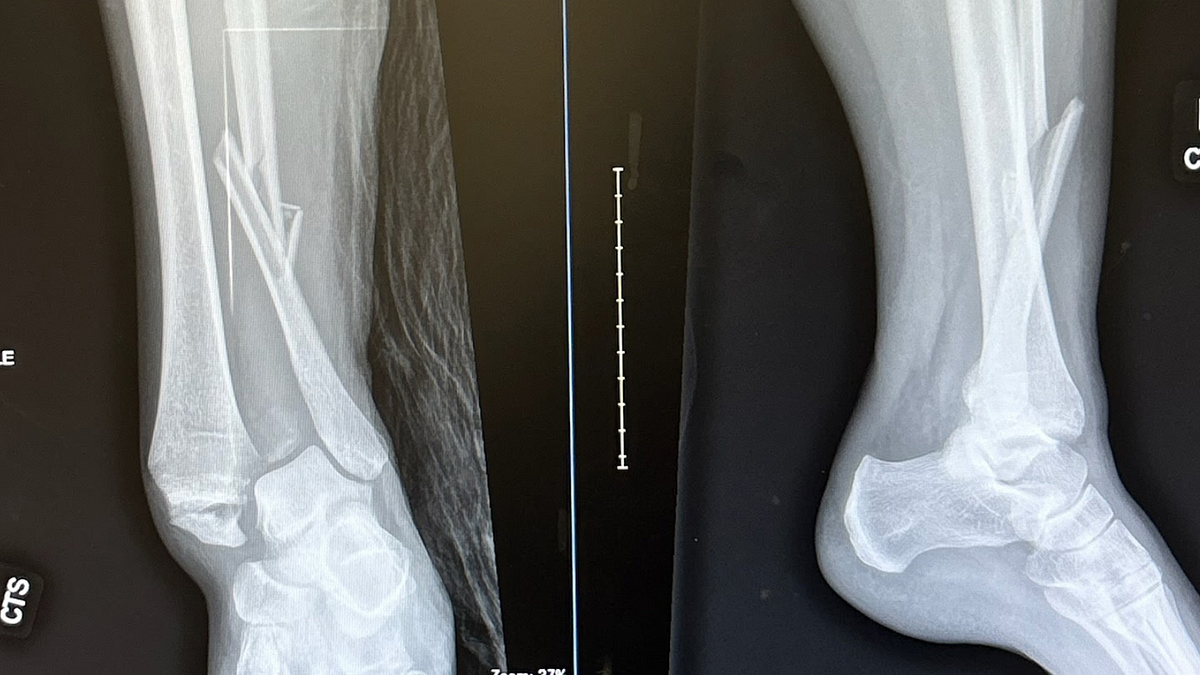

I broke my leg and learned some hard UX lessons

The world is even less accessible than I thought.